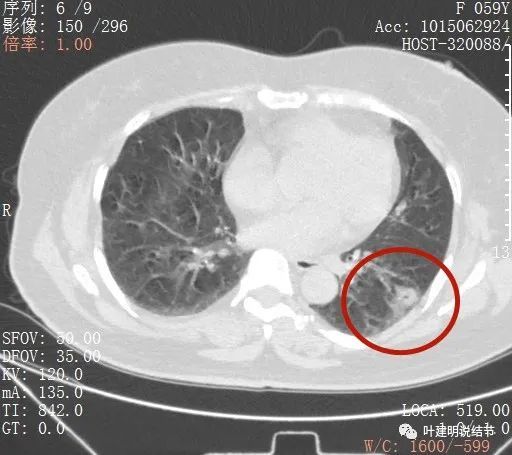

肺癌中期,肺癌中期检查通知书

10.31):虽然是典型的肺癌,但看片子总

左肺iv期19突变肺癌患者的一丝精准化治疗

肺癌ct

肺癌ct图片